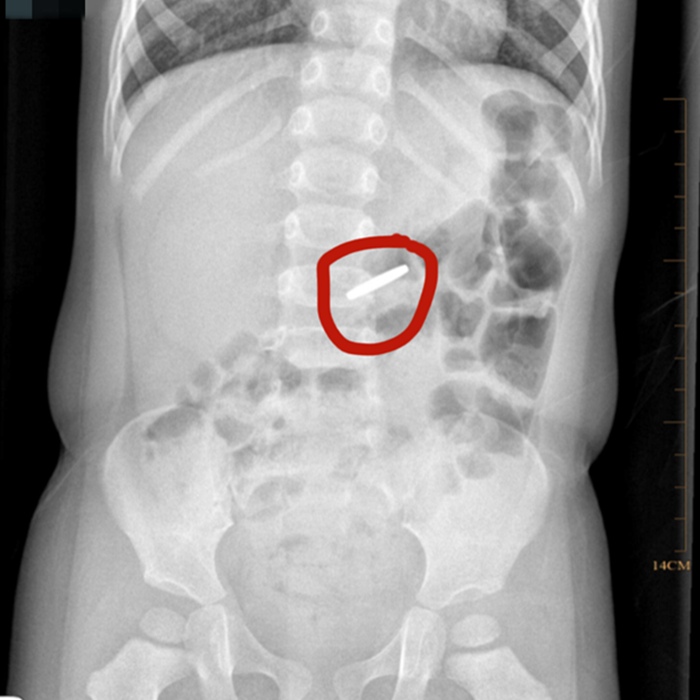

溫附二兒科消化專家胡偉國主任醫(yī)師會診后,立即為小京京開具X光片檢查,發(fā)現(xiàn)異物滯留于胃部,考慮到硬幣長時(shí)間在胃內(nèi)可能引起胃黏膜損傷,胡偉國馬上聯(lián)系麻醉科、內(nèi)鏡中心,在靜脈麻醉下為小京京行內(nèi)鏡下胃內(nèi)異物取出術(shù)。

術(shù)中發(fā)現(xiàn)硬幣果然還在胃里,好在胃黏膜無受損,胡偉國主任通過專用異物鉗很快將硬幣取出。該硬幣直徑約19毫米,已被胃液略微腐蝕。